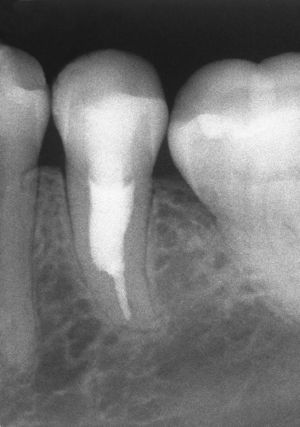

SintomatologíaLos dientes afectados pueden permanecer asintomáticos durante mucho tiempo. La prueba de sensibilidad puede ser positiva o negativa en función de la localización. Las profundidades de sondaje no están alteradas y no se observa movilidad dentaria. El diagnóstico suele ser el resultado de un hallazgo radiográfico casual (figs. 3 y 4) o producirse a raíz de una perforación y de una infección secundaria por la expansión del proceso original. El proceso se puede transparentar en forma de mancha rojiza («pink spot») si la laguna de reabsorción se localiza en la zona de la corona.

Las reabsorciones internas se caracterizan por los signos radiográficos siguientes:

Ensanchamiento oval de la luz del conducto.

Lesión bien delimitada.

Lesión simétrica.

Posición estacionaria incluso en una proyección radiológica excéntrica complementaria.

Espacio periodontal continuo.